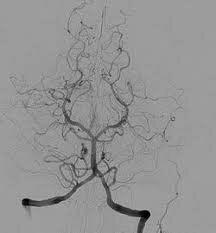

• Angiografía digital

Angiografía digital

Durante esté año surgió la angiografía digital, la cuál a evolucionado el camino del estudio y tratamiento de patología.

Permitiendo grandes avances para la medicina a la hora de detención de enfermedades.